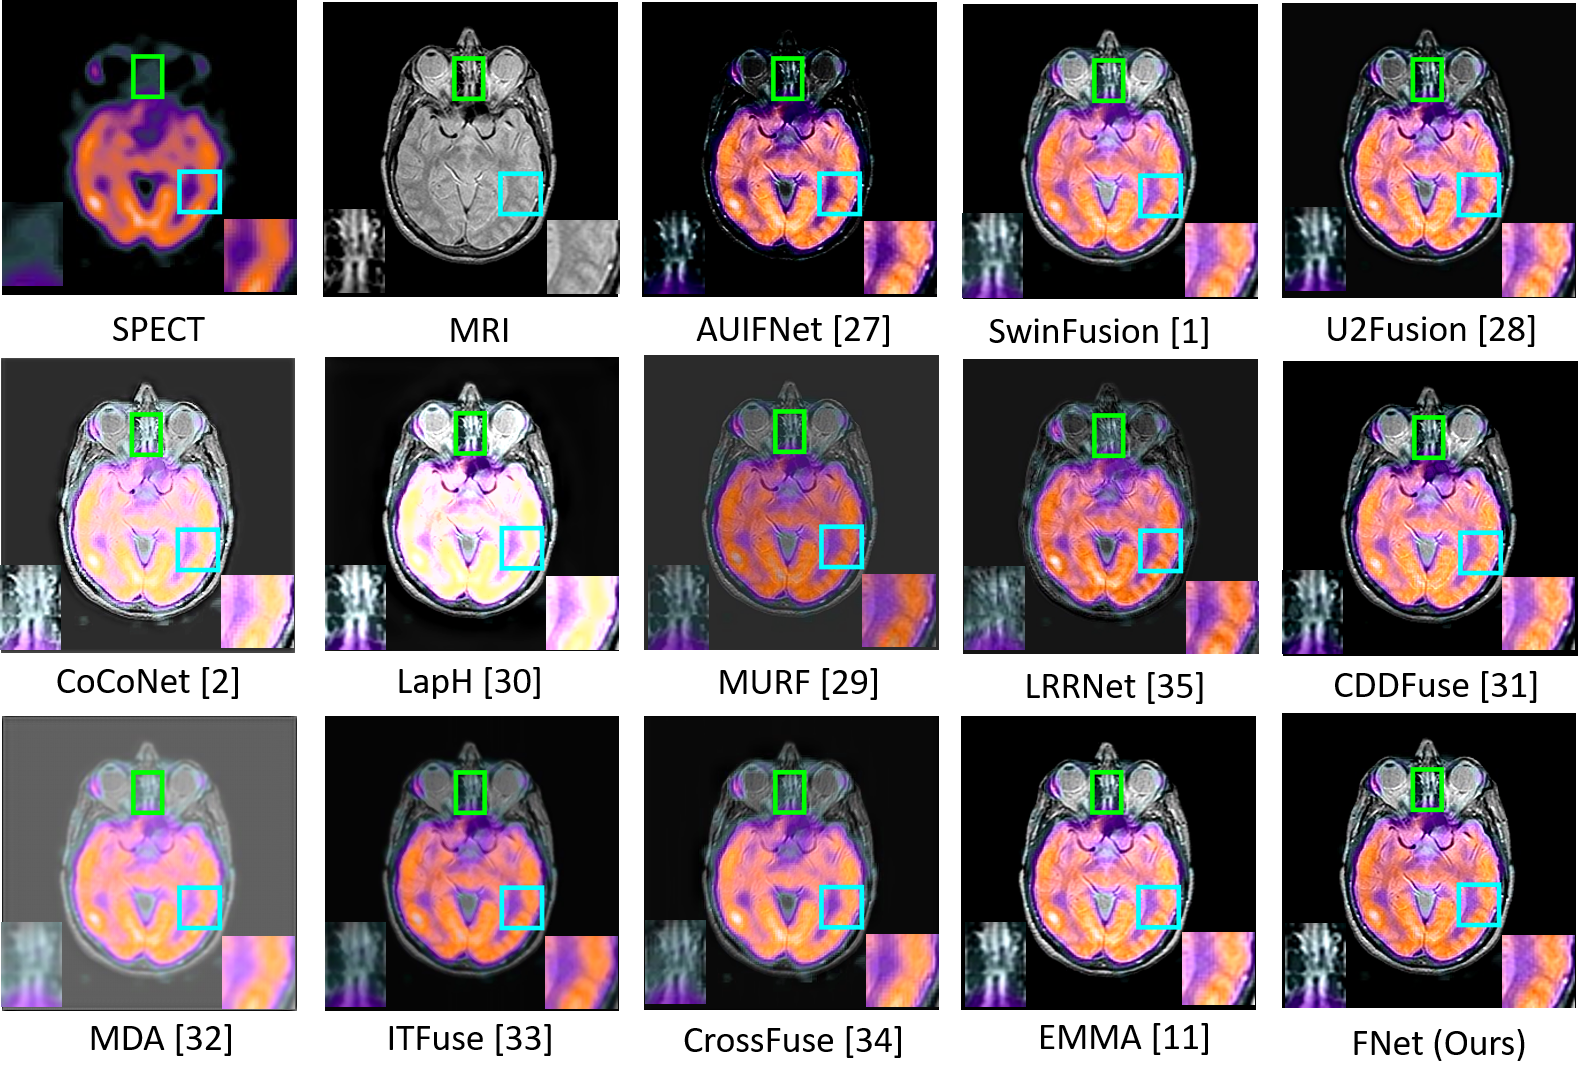

FNet is compared with twelve recent SOTA methods: AUIFNet [27], SwinFusion [1], U2Fusion [28], CoCoNet [2], LapH [30], MURF [29], LRRNet [35], CDDFuse [31], MDA [32], ITFuse [33], CrossFuse [34], and EMMA [11].

Fig. 7 shows a visual comparison of the SPECT-MRI image fusion task on the Harvard medical dataset. Our FNet effectively separates the common edge details in the SPECT-MRI image pairs, the unique functional details in the SPECT image, and the tissue details in the MRI image and combines all these features into the fused image. Compared to the SOTA methods, FNet can better preserve the tissue and structure details of the source images. More visual comparison results are given in the supplementary material.